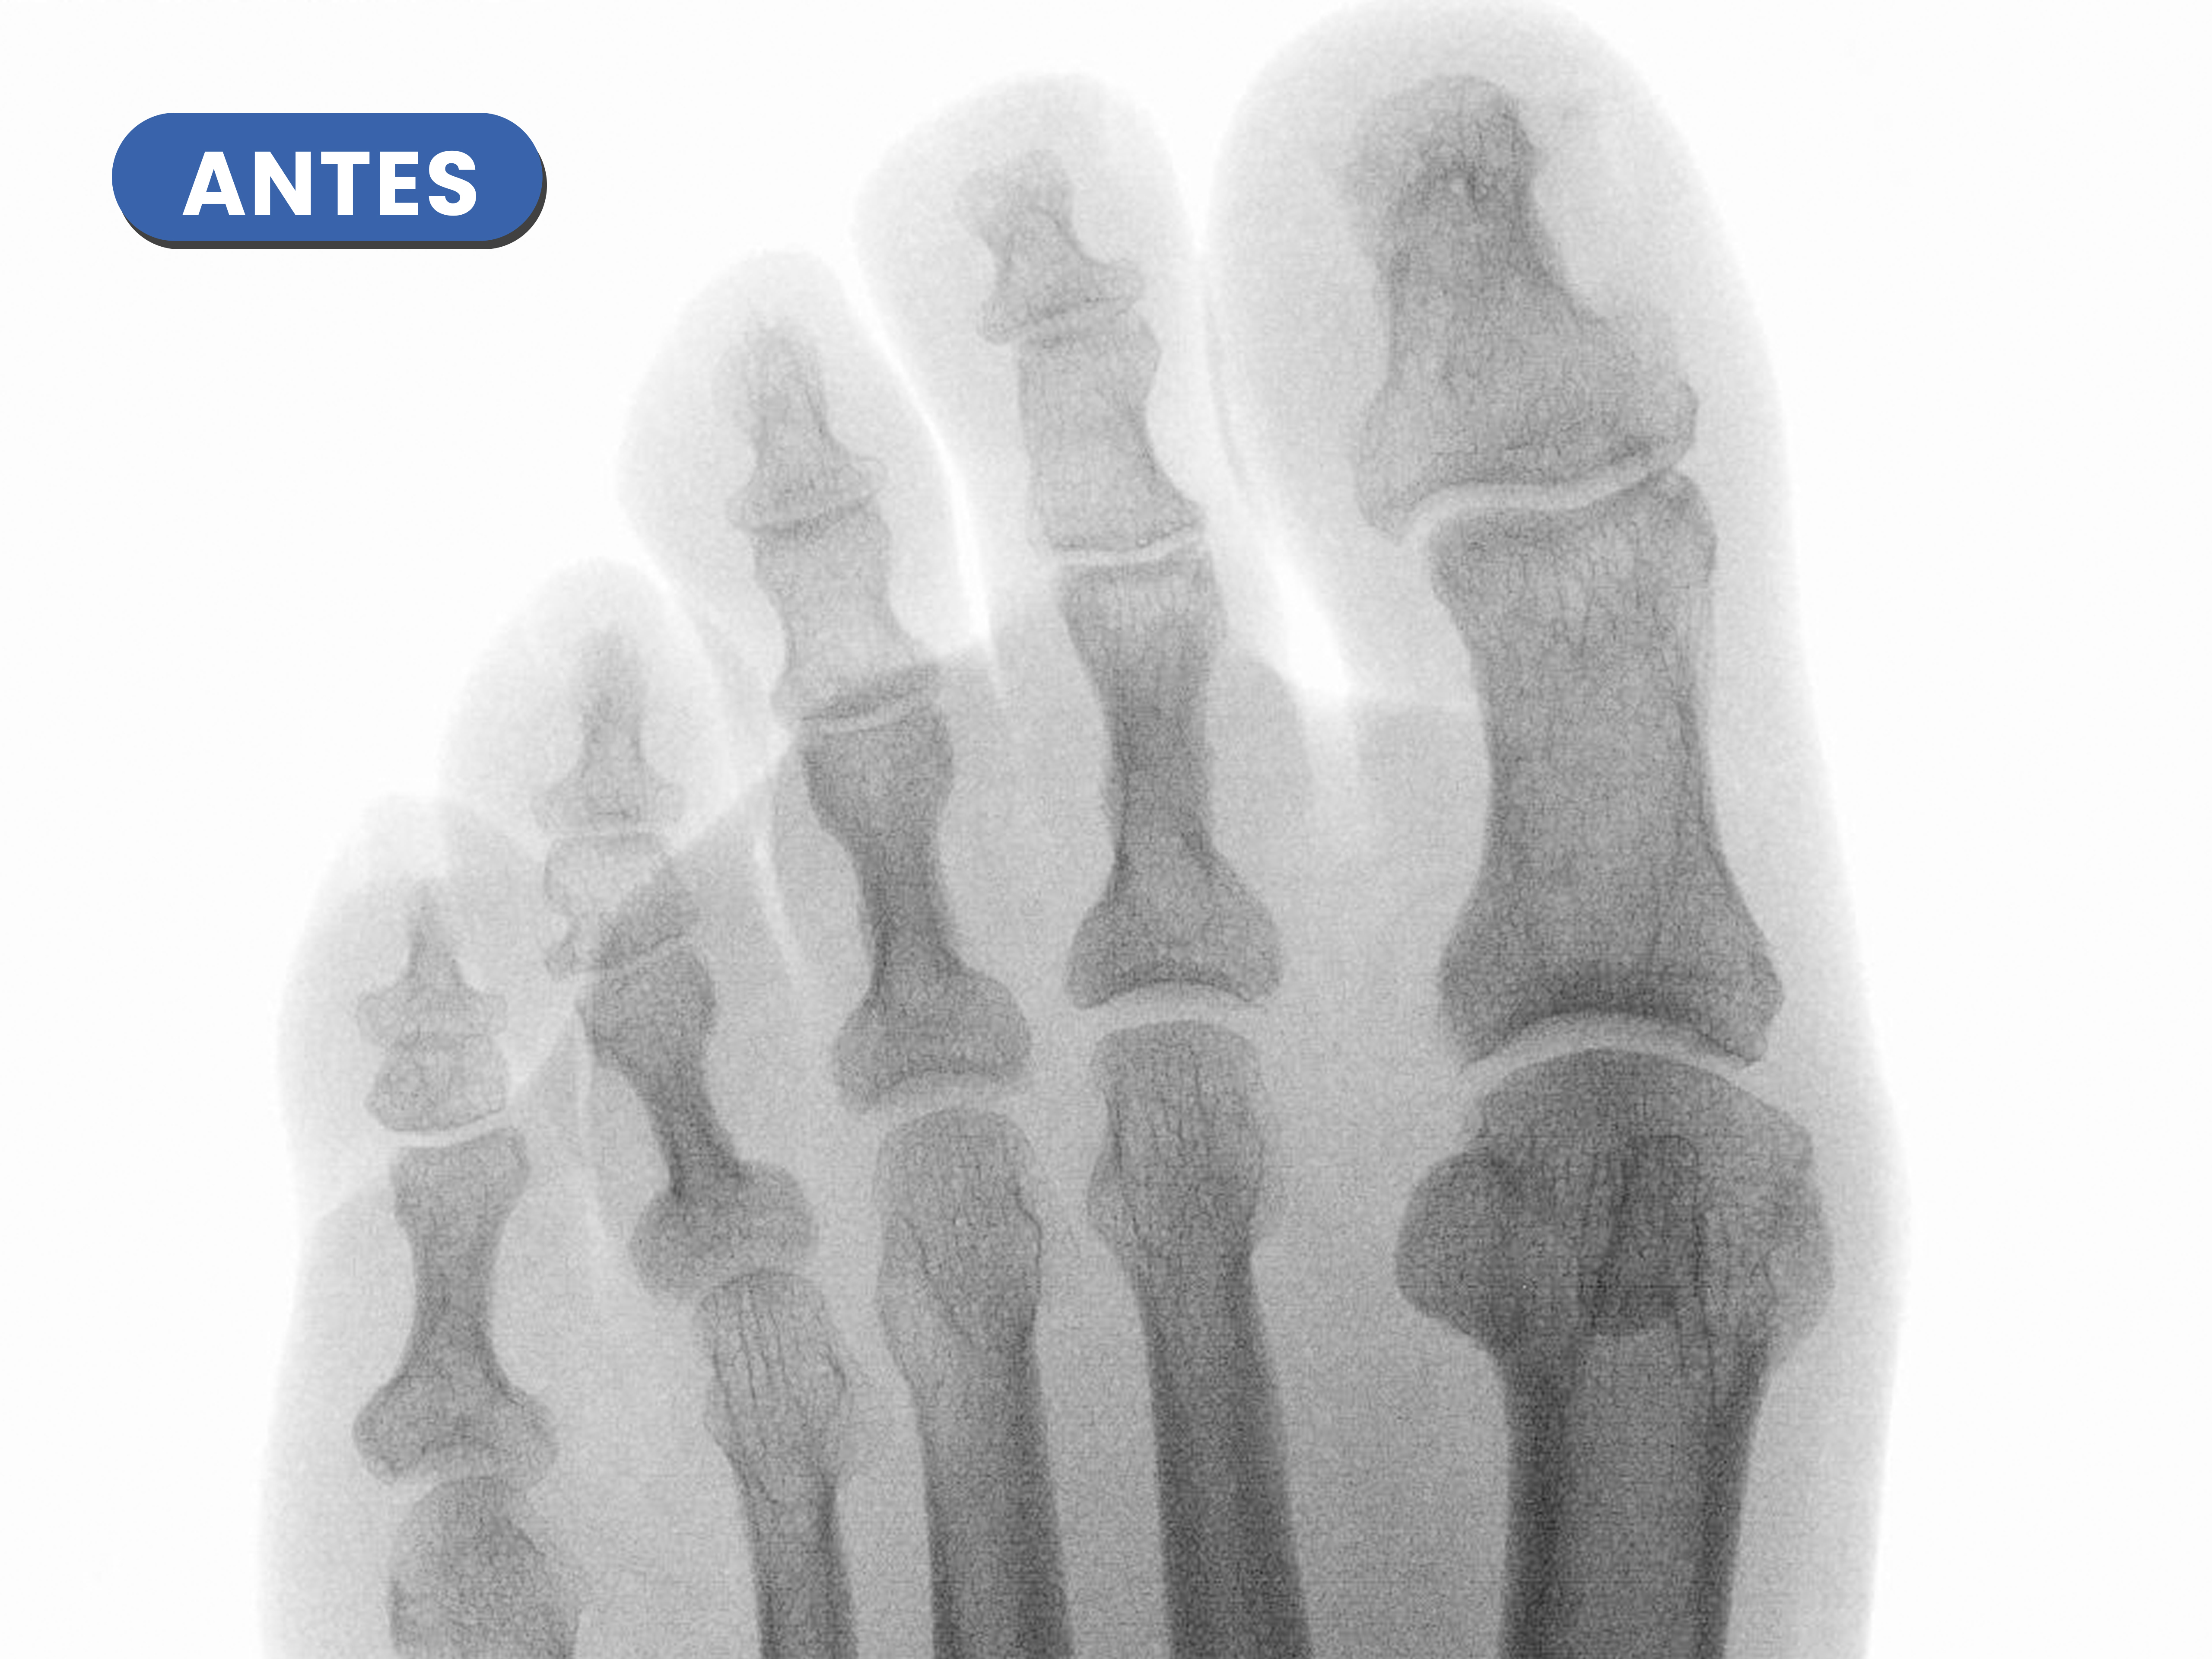

Casos reales resueltos con Cirugía de Mínima Incisión (CMI)

Te mostramos casos reales resueltos mediante cirugía de mínima incisión por el Dr. Rubén Lorca y su equipo.

Mueve las flechas para visualizar el antes y después.